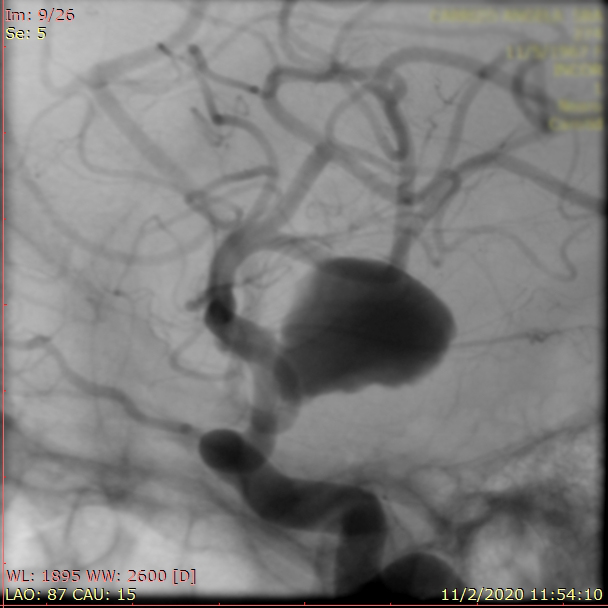

La paciente ingreso al Servicio de Hemodinamia el día martes 11 de febrero con un aneurisma cerebral gigante en la carótida izquierda y se le practicó una embolización; es decir una oclusión por dentro del mismo, donde se colocó un dispositivo denominado coils más un stent diversor de flujo. El procedimiento fue exitoso y contó con la colaboración de médicos neurointervencionistas del Instituto Oulton de la Ciudad de Córdoba.

La paciente llevaba un tiempo refiriendo dolores de cabeza, trastornos visuales por lo cual luego de realizarcele los estudios pertinentes y comprobar la patología se programó el procedimiento. Debido a que el Hospital Vera Barros no contaba con la tecnología necesaria para esta práctica compleja es que se realizó en la nueva Sala de Hemodinamia de INCOR en el marco de un convenio de trabajo conjunto entre la salud pública y la privada.